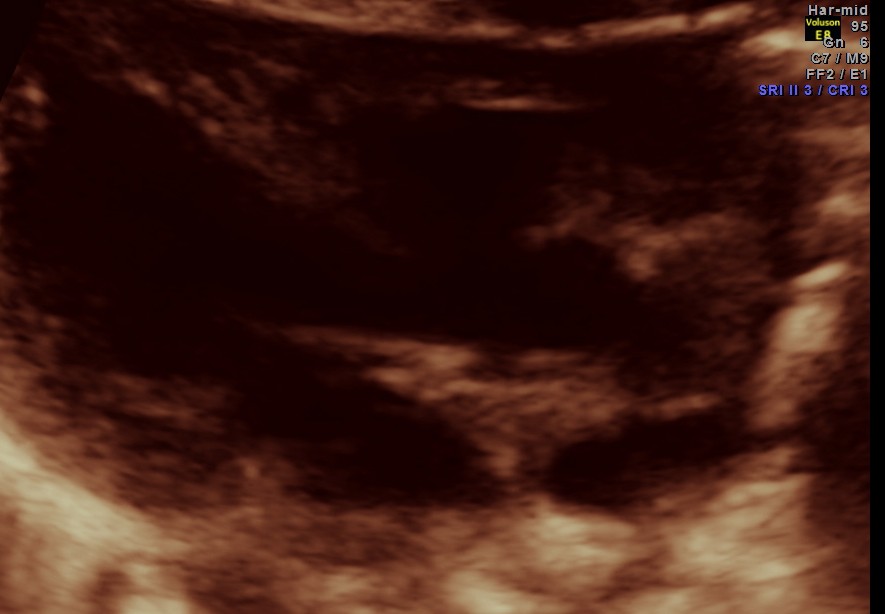

The following pictures are of the heart of the child .